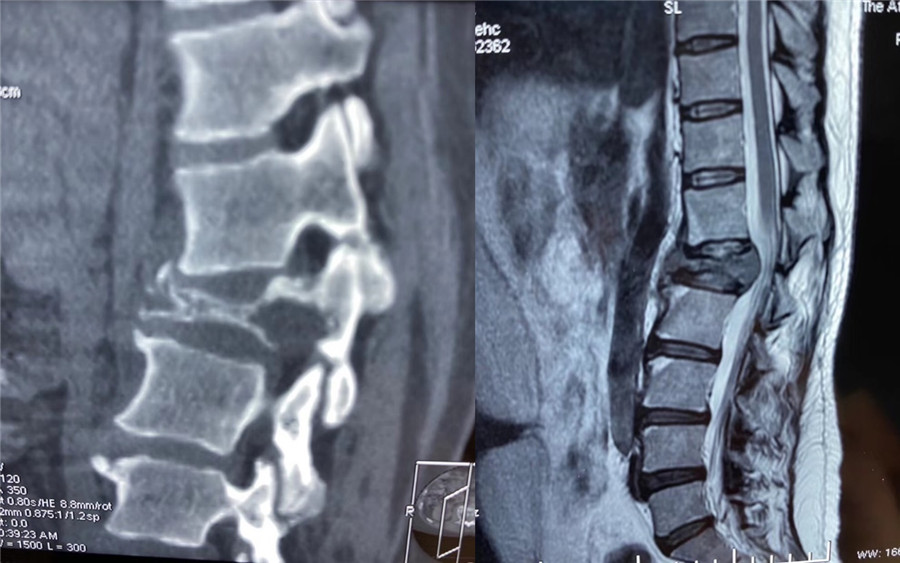

近日,91直播 脊柱外科赵岩团队收治一名因腰背痛并逐渐加重的患者,该患者4年前因乳腺癌行保乳手术治疗,后因经济原因未进一步作放化疗,此次详细辅助检查后高度怀疑为腰1椎体转移瘤,肿瘤椎体及附件骨质已被严重侵蚀,随时会有脊髓被进一步压迫而导致患者瘫痪的可能。

该患者家庭经济拮据,且疫情期间无法外请北京专家前来手术,患者及家属辗转自治区多家医院找到赵岩医生,赵岩团队经过反复讨论和充分准备,最终在麻醉科(手术室)紧密配合下独立完成一期后路固定+En-bloc腰1椎体肿瘤切除术+椎体重建术,该手术首先行后路脊柱固定,其次从后方经椎弓根将病变节段的后部结构整块切除,再向前方分离骨膜和椎体周围血管(这是手术风险最大的步骤),分离彻底后将椎体一并整块切除,最后重建脊柱前中柱。

术前